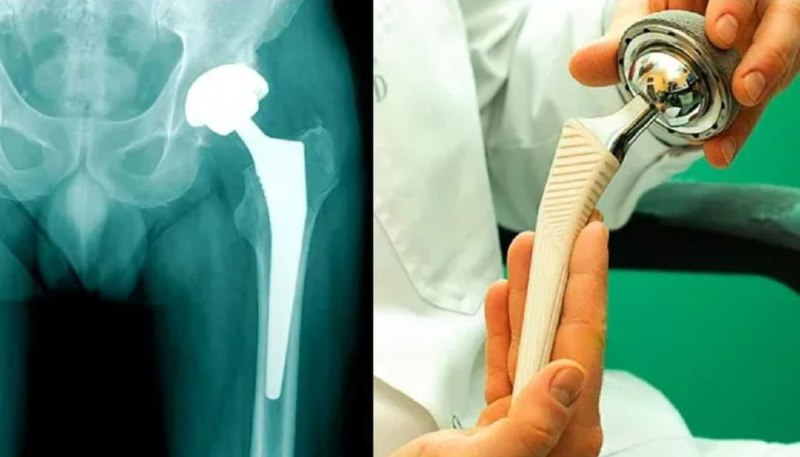

Восстановление после эндопротезирования тазобедренного сустава: что важно знать в первые дни

Эндопротезирование — серьёзная операция, и первые дни после неё особенно важны для успешного восстановления. В этот период организм ослаблен, вы ещё не полностью отошли от наркоза, а значит — нужно быть особенно внимательным к своему телу, особенно к прооперированной ноге.